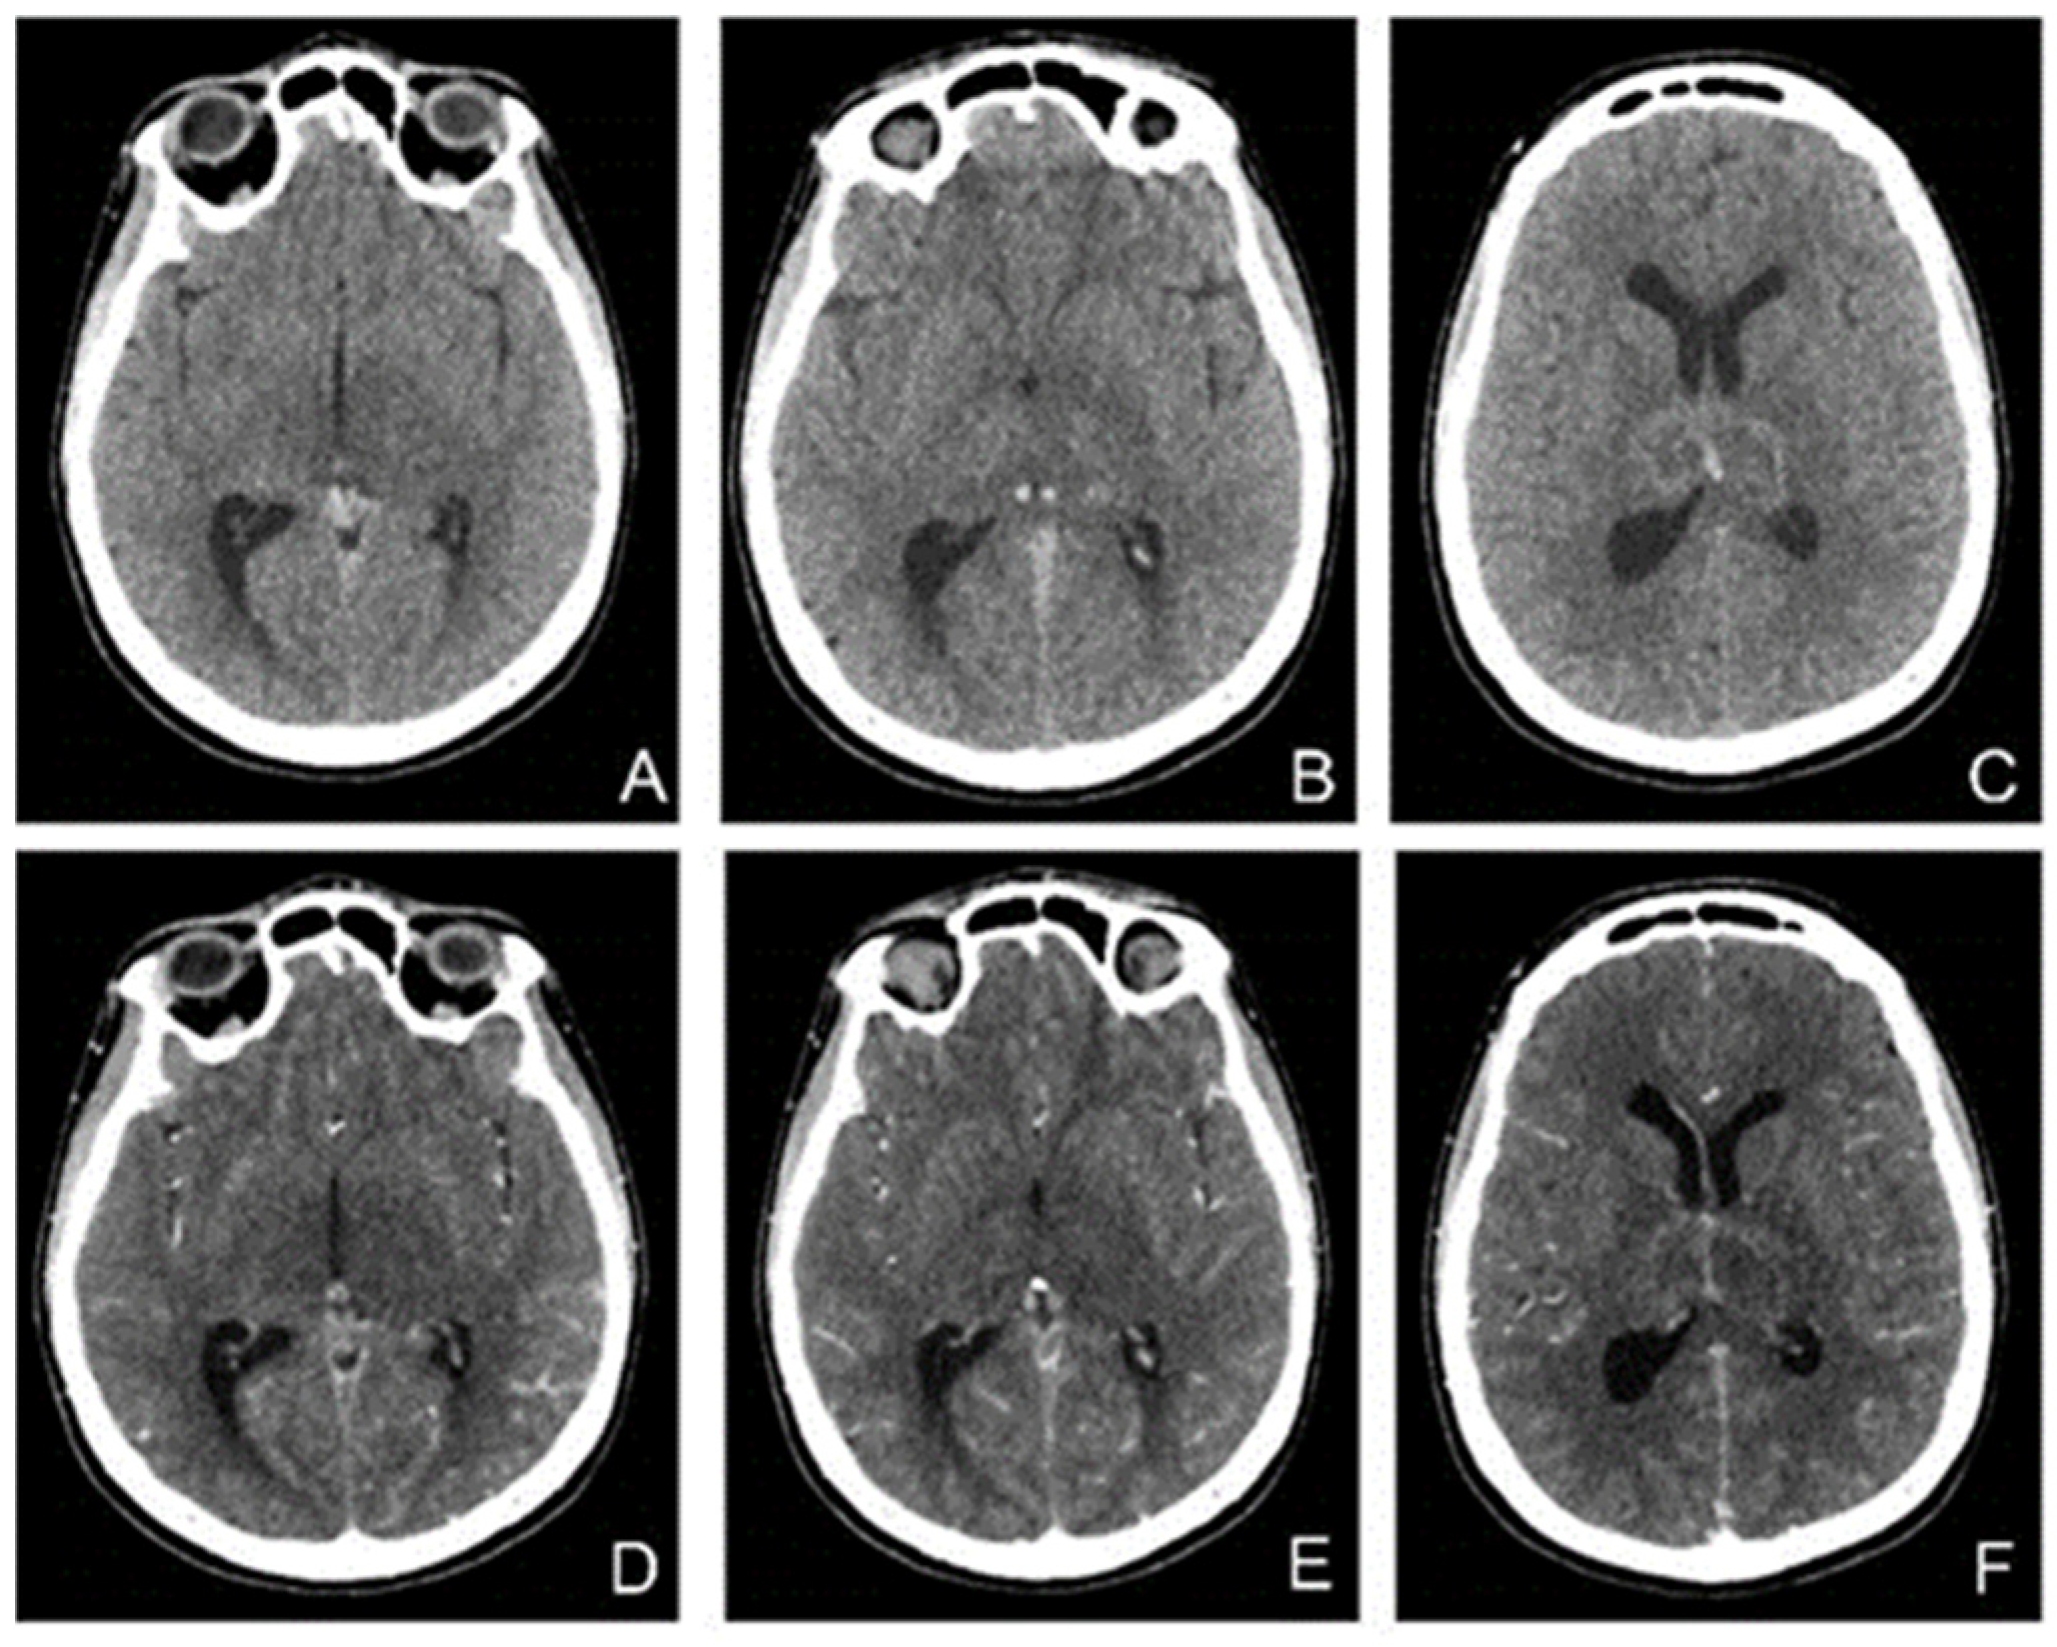

MRI showed (Figure 6) changes evoking venous thrombosis of left transverse and sigmoid sinuses, straight sinus, vein of Galen, internal cerebral and basal veins with extensive venous infarcts at the level of bilateral basal ganglia and a left temporo-occipital subcortical area.

In the following days, the patient′s condition continued to worsen. She did not respond to nociceptive stimuli, spontaneously mobilized her limbs, and had involuntary movements of the jaw. Considering the unfavorable and unpredictable evolution, in agreement with the family, we decided to perform therapeutic abortion. A new brain CT was performed (Figure 7).

Figure 6. MRI without contrast enhancement ((A)—T2 axial, (B)—FLAIR coronal, (C)—DWI axial, (D)—ADC axial, (E)—venous TOF sagittal) shows hyperintensities of the thalamic nuclei on T2, FLAIR and DWI, with areas of restricted diffusion included and no flow in Galen’s vein, internal cerebral veins, straight sinus, and inferior sagittal sinus.

Figure 7. CT without contrast (AC) and with (DF) contrast enhancement shows hyperdensities in the Galen vein and internal cerebral veins with nonhomogeneous thalamic nuclei. After contrast enhancement, there was a slight enhancement in the veins and hypoperfusion of the thalamic nuclei.